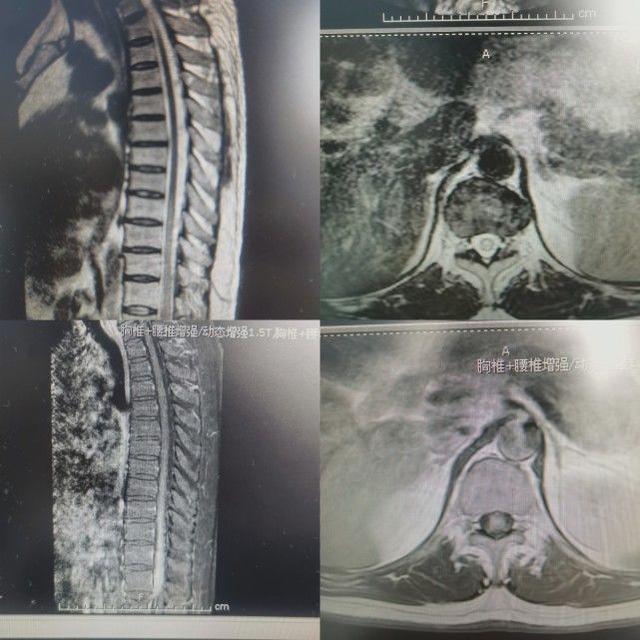

脊髓血管畸形

43岁的杨先生,2个月前出现双下肢麻木等症状,入院前一天症状加重。医院完善相关检查后最终诊断为脊髓血管畸形。给予减轻水肿、改善循环、营养神经、缓解神经痛等对症治疗,肢体症状改善较弱,目前需进一步脊髓血管造影检查。